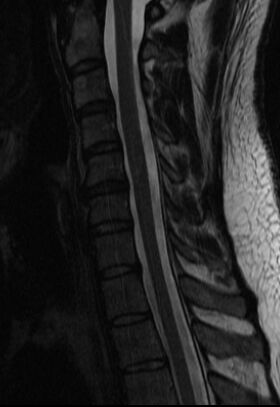

Nyakamon kicsik de sok van,

Hátamba kettő, ebből az alsó eléri a gerincvelőt,

Derekam szanaszét trancsírozva, foramen szűkületek, deformált, stb,

Legutóbbi rtg. idegsebész elismerte hogy a felvételen is látszik az erősen jobbra dőlő gerinc kénszertartása, ami a fájdalmat jelzi és hogy baj van. De hogy mi a baj azt nem tudja.Hogy ezekből ki mit látott meg ki mit nem, azt nem tudom. De ha műteni akarnak nem fogok bele egyezni. Elég volt a segítségükből.

elég érdekes, mri-t jó lenne látni, mégis mi az, ami nem utal műtétre, de gondot okoz.

mi nyomja akkor az ideget? a csavarok? -